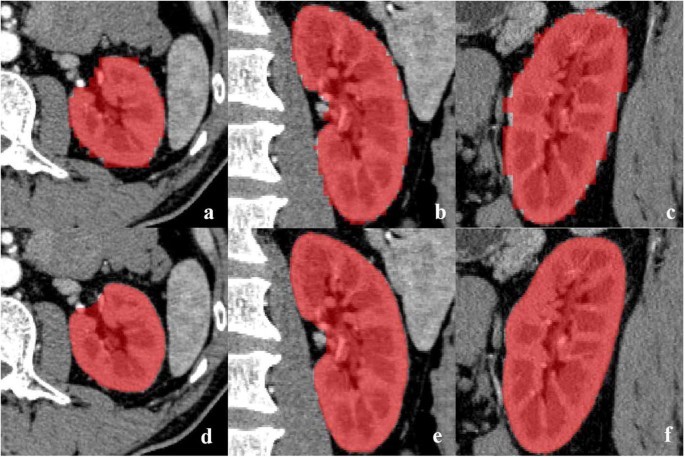

o Ultrasound: Initial screening for cysts/masses.

o CT Scan: Detailed X-ray images to explore tumors, size, spread.

o MRI: Detail soft tissue imaging, usage when CT was not ideal.

• Biopsy: To confirmed cancer cells, a tissue sample taken with needle.